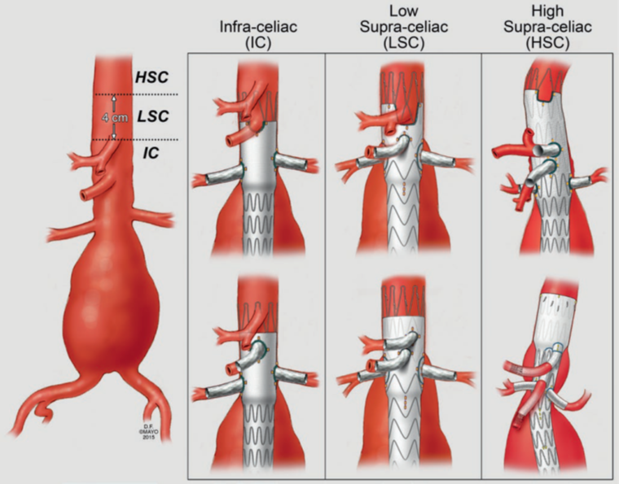

Fenestrated Endovascular Custom Made Device

Εξειδικευμένο ενδαγγειακό μόσχευμα

Τα αγγεία που φεύγουν από την αορτή και δίνουν αίμα στα διάφορα όργανα, έχουν διαφορετική ανατομία σε κάθε ασθενή.

Στόχος του εξειδικευμένου ενδαγγειακού μοσχεύματος είναι να καλύψει όλη την έκταση του ανευρύσματος πέρα από τις αρτηρίες αυτές, αποκλείοντας έτσι το ανεύρυσμα από την κυκλοφορία του αίματος και μειώνοντας με αυτό τον τρόπο δραστικά το ρίσκο για μελλοντική ρήξη και τον θάνατο